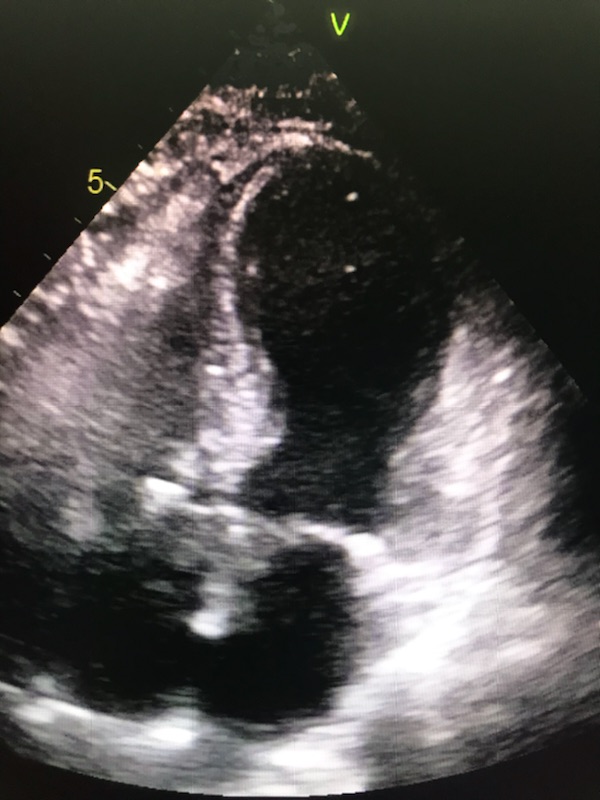

2d Echocardiogram Takotsubo Cardiomyopathy Youtube